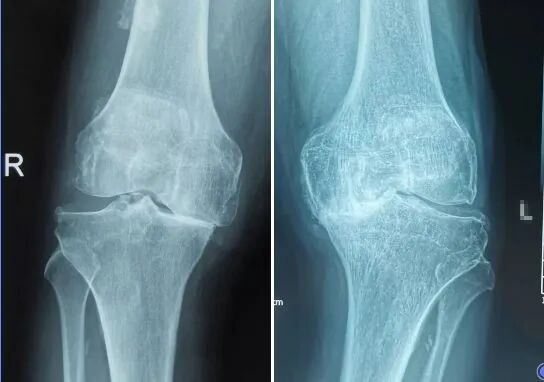

作者供图(膝关节骨性关节炎表现:关节间隙不对称或者变窄,边缘骨质增生和骨赘形成,可见膝内翻畸形)

老寒腿是不穿秋裤导致的?为啥有人天一冷就膝关节疼?关于老寒腿,下面这些知识你需要知道。 老寒腿其实就是膝关节骨性关节炎,是一种常见的慢性关节疾病,并不是风湿引起。 特征是膝关节软骨退行性变,包括关节软骨的磨损和关节软骨的变性退化,以及骨质增生等引起的关节疼痛和关节功能障碍。 从字面上看“老寒腿”这三个字的叫法比较确切: 老是多见于年纪大的患者,病程长容易反复发作; 寒就是怕冷,遇到冷天、冬天的时候,疼痛会加重,需要穿更厚的衣服; 腿是疼痛的部位,位于膝关节。